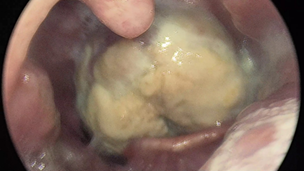

using a tongue depressor revealed a large bulging mass rising from the

posterior wall of the pharynx, posterior and inferior to the left posterior

tonsillar pillar. The overlaying mucosa was unevenly covered with a white

membrane. Indirect laryngoscopy showed a sizable mass towering above the

bent-forward epiglottis. (Figure 1)

Figure

1. Clinical examination showing a

bulging mass rising from the posterior wall of the pharynx